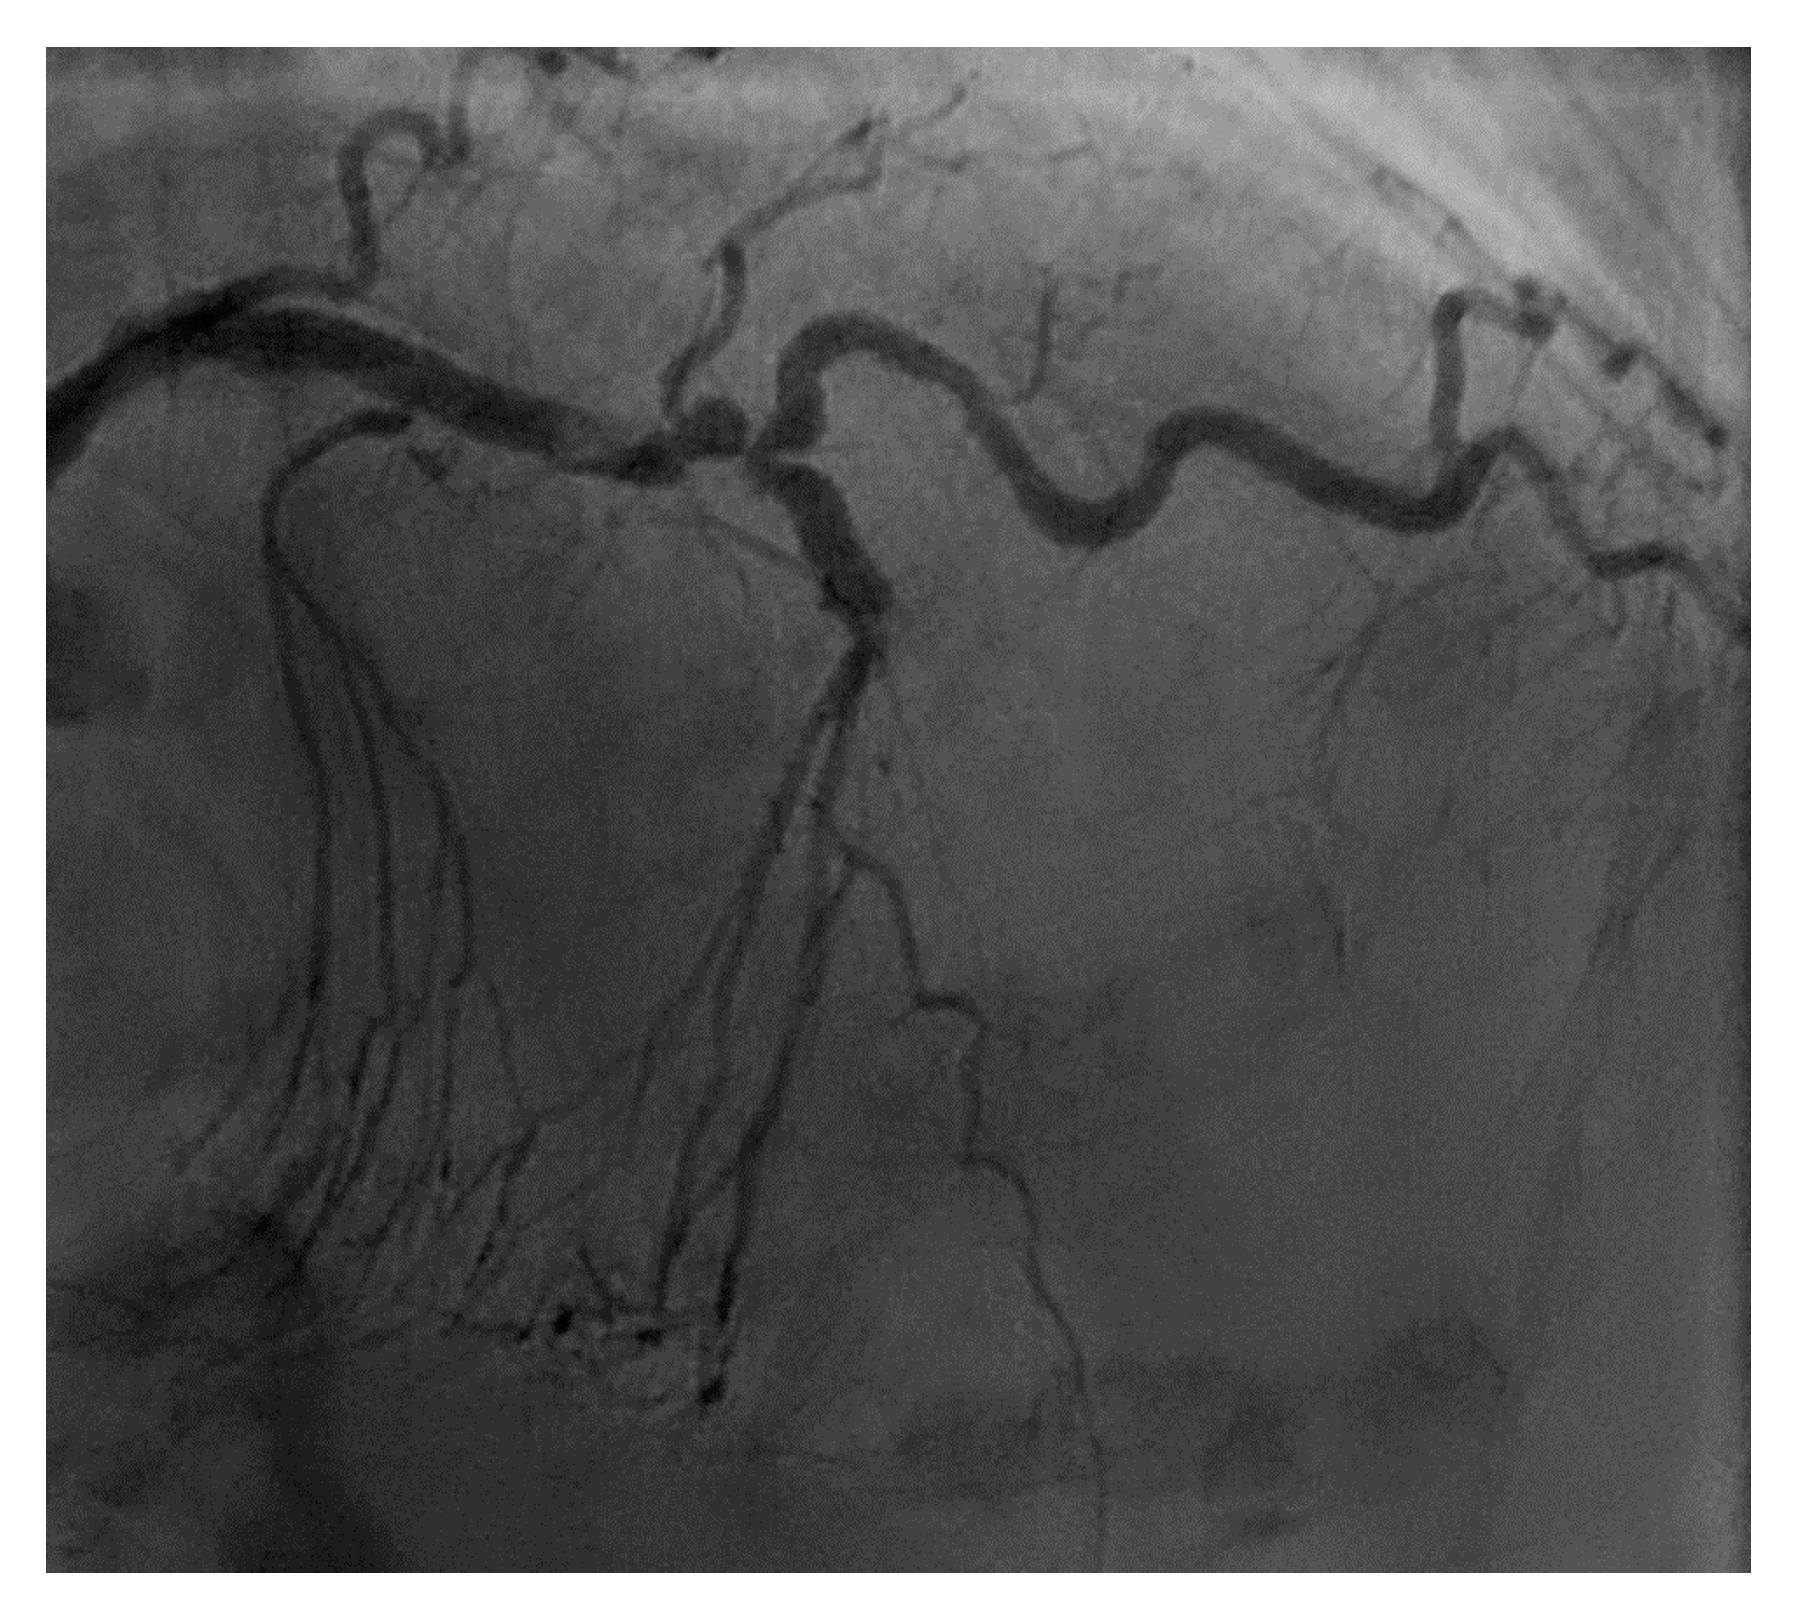

Figure 4. This is an example of a poor choice for robotic PCI. The patient has a single coronary artery with an ejection fraction of 20% and the lesion is very complex in the artery with severe tortuosity and angulation.